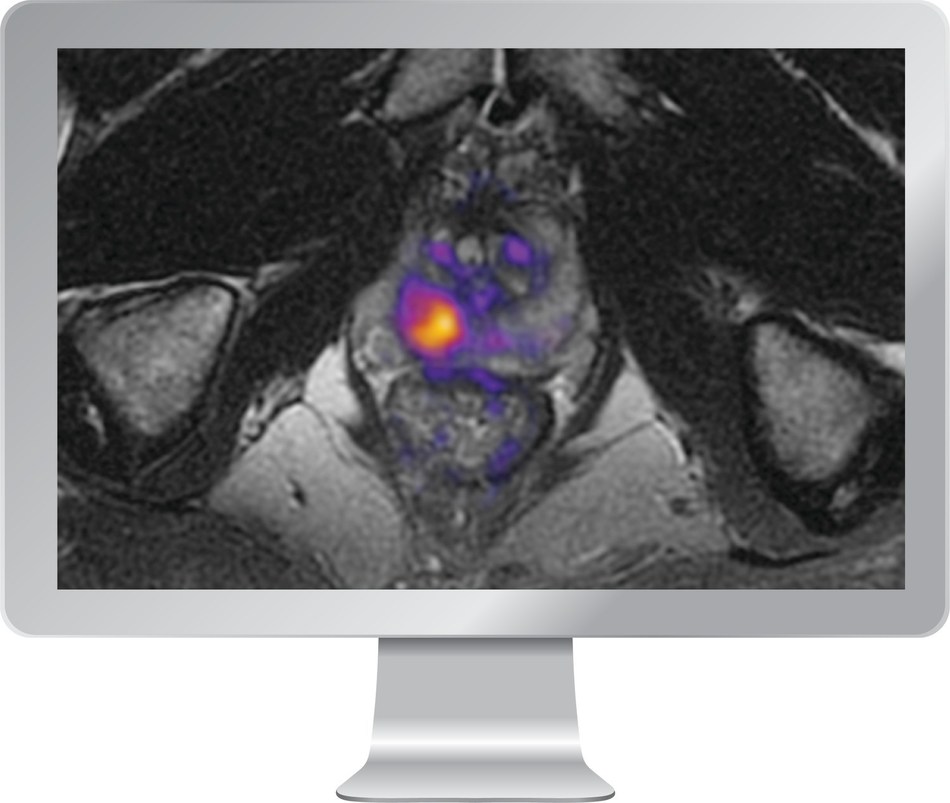

RSI-MRI+ imaging software utilizes an advanced diffusion MRI technique, biophysical models, and artificial intelligence to increase the visibility of restricted water, a hallmark feature of cancerous tissue.

RSI-MRI+ utilizes a patented advanced diffusion MRI technique called Restriction Spectrum Imaging (RSI) to help improve early detection and diagnosis of prostate cancer by clinicians. It is the first FDA-cleared imaging software to use artificial intelligence and an innovative tissue microstructure model to increase the visibility of restricted water in the body's tissue.

Many cancers, including prostate cancer, are highly cellular tissues that trap or restrict water. A limitation of conventional diffusion MRI is that it doesn't directly measure restricted water, but instead relies on a simpler measure known as the apparent diffusion coefficient (ADC). While the ADC is an important biomarker, it's affected by a number of confounding factors that can negatively impact its sensitivity and specificity to cancer, which can result in missed or inaccurate diagnoses.

"A key innovation of RSI-MRI+ is that it can better characterize the complexity of water diffusion in cancerous tissue, resulting in better performance," said Nathan White, PhD, CEO of HealthLytix and co-inventor of RSI. "With early-stage aggressive cancer, we need more sophisticated approaches to separate what's important from what's not important. In cancer, that means separating restricted diffusion from other sources of water diffusion that are less relevant."